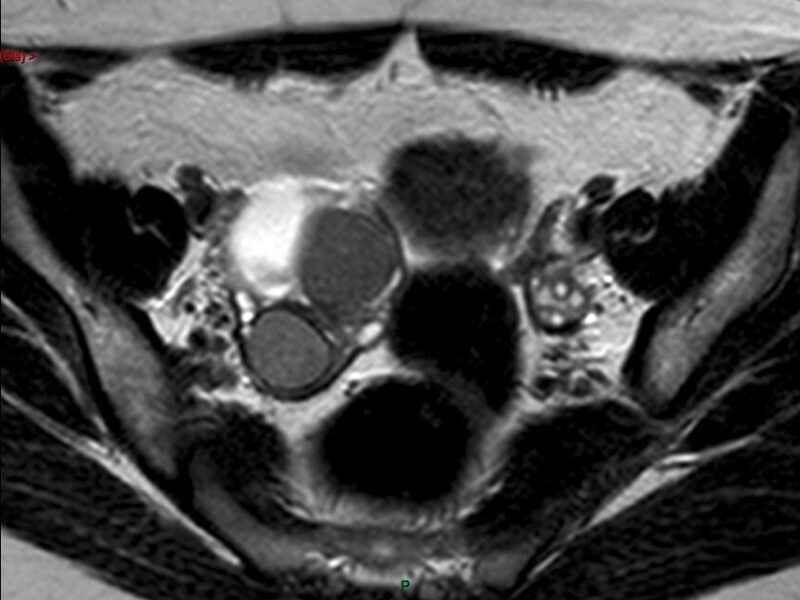

« Il est essentiel d’apprendre à reconnaître les signes spécifiques de l’endométriose »

Dans le cadre de mars jaune, le mois de sensibilisation à l’endométriose, l’hôpital Paris-Saint-Joseph (75) a organisé le 6 mars une journée de sensibilisation à l’endométriose, ainsi que d'autres ...